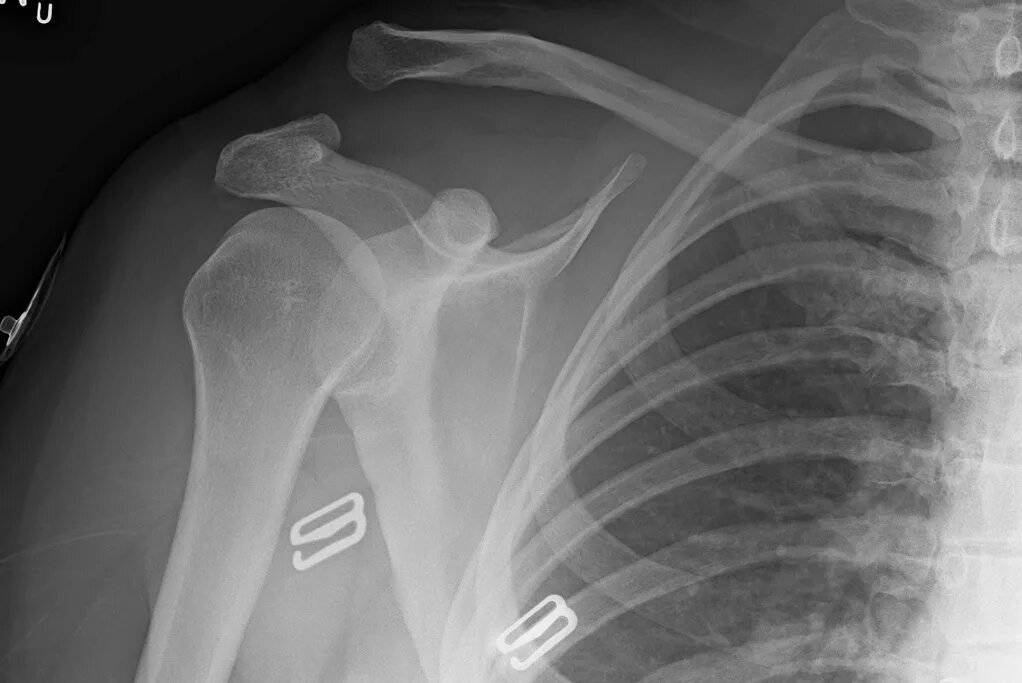

Вывих акромиально ключичного сочленения